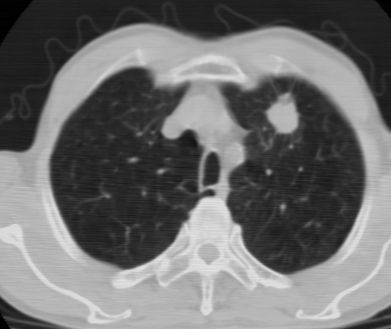

标题: CT24783:m71,既往肺心病史3年,现咳嗽,憋喘。 [打印本页]

标题: CT24783:m71,既往肺心病史3年,现咳嗽,憋喘。

1、左肺上叶spn,毛刺+分叶+血管集束征,考虑周围型肺癌可能性大

2、全小叶性肺气肿。

1)左肺上叶周围型肺癌可能。2)两肺全小叶型肺气肿。

左上周围型肺癌,全小叶型肺气肿。